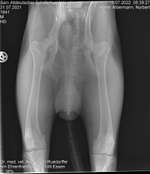

Mein kleiner Spatz hat seit gestern Speichelfluss, ich habe auch in sein Maul geschaut ob vielleicht was zwischen den Zähnen hängt, hab da aber jetzt nichts gesehen., er spielt und isst ganz normal., er zeigt mir keine Krankheitssymptome. Wenn's bis morgen nicht weg geht würde ich zum Tierazt fahren ...